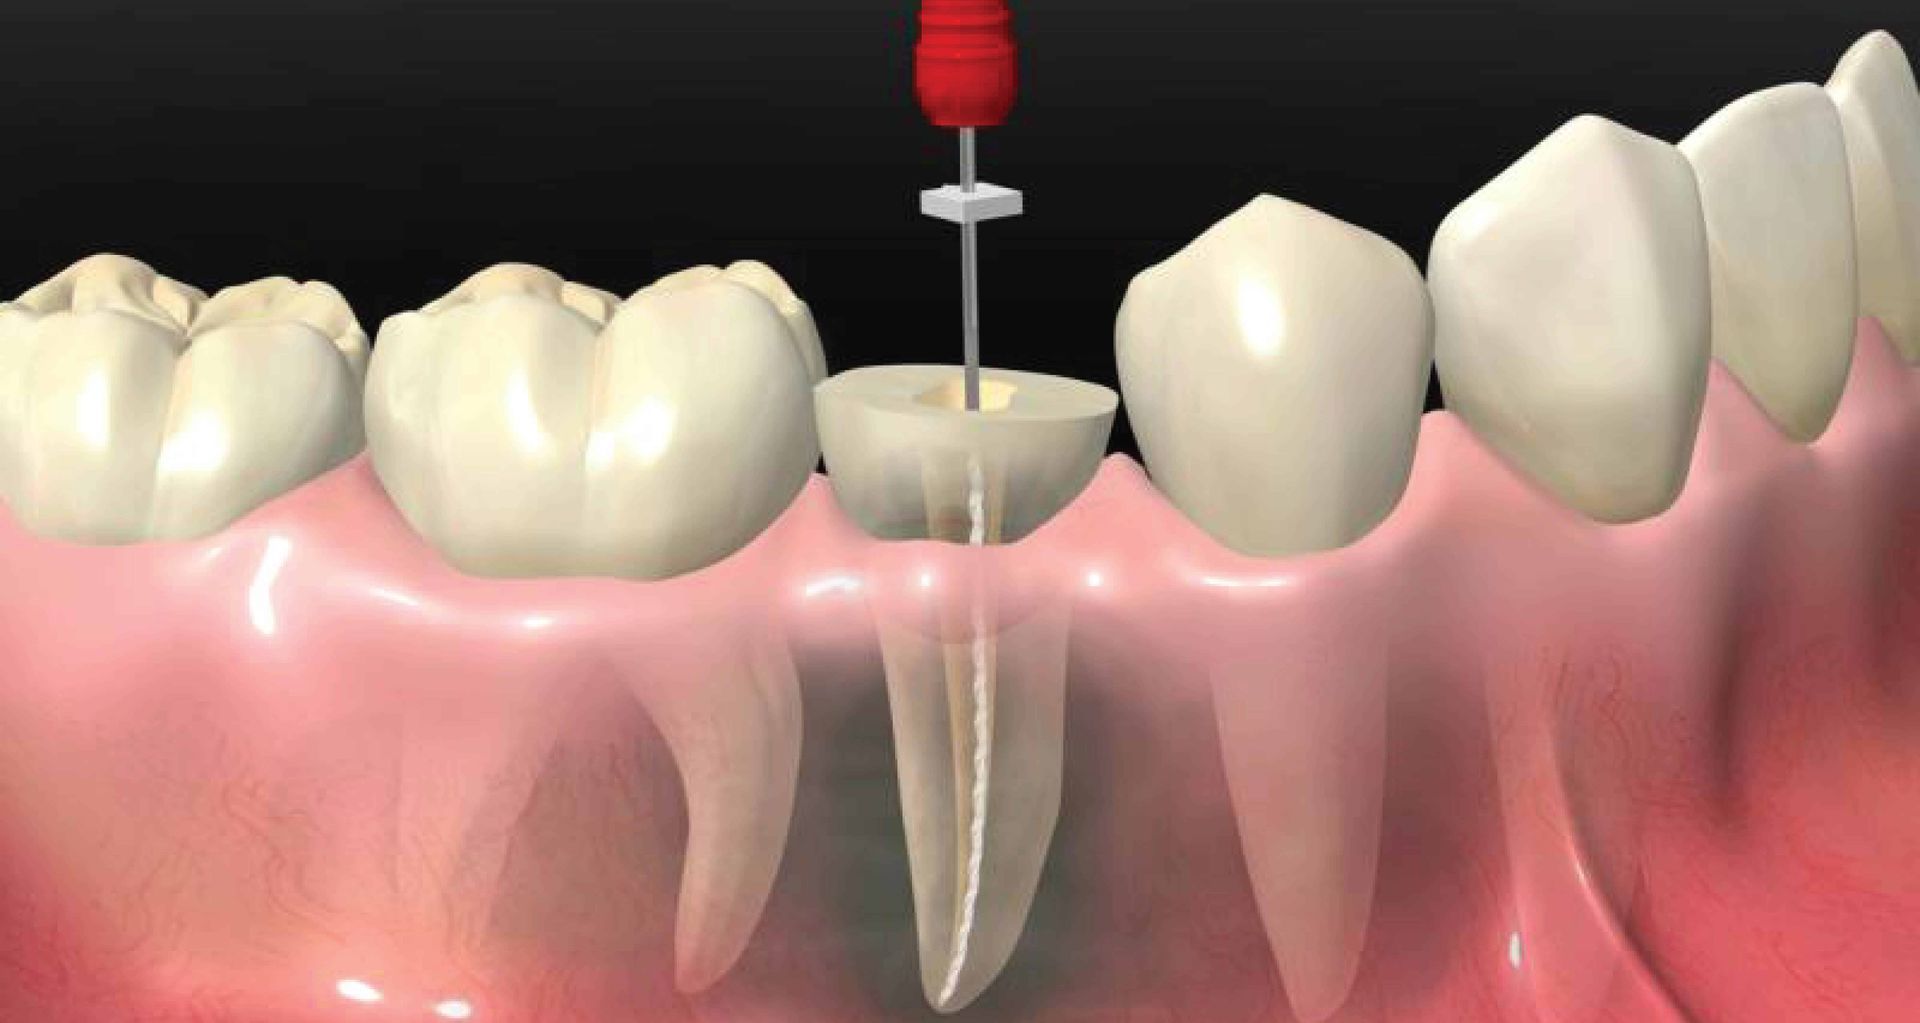

During a root canal, the dentist begins by numbing the area to help ensure comfort. An opening is made in the tooth to access the pulp chamber and root canals. The infected or inflamed pulp is removed, and the canals are cleaned and shaped. After disinfection, the canals are filled with a biocompatible material and sealed to help prevent reinfection. In most cases, the procedure is completed over one or more visits, depending on the tooth’s condition and complexity.

How Root Canals Work

Root canal treatment (RCT) is a way of retaining a fully functional tooth that would otherwise be lost. A root canal is performed over several visits, depending on the particular case:

Visit 1: An opening is made at the top of the tooth to access the nerve and eliminate the pain.

Visit 2: The chamber and root canals are cleaned and slightly enlarged, and medication is placed in the canal and sealed for a period of time.

Visit 3: The canals are sealed with a rubbery filling material and the tooth is then restored.

Root canal treatment is now a routine dental treatment, and with good anaesthesia, it is relatively painless. The introduction of rotary files in recent times has improved the process, making it more comfortable than it was years ago.